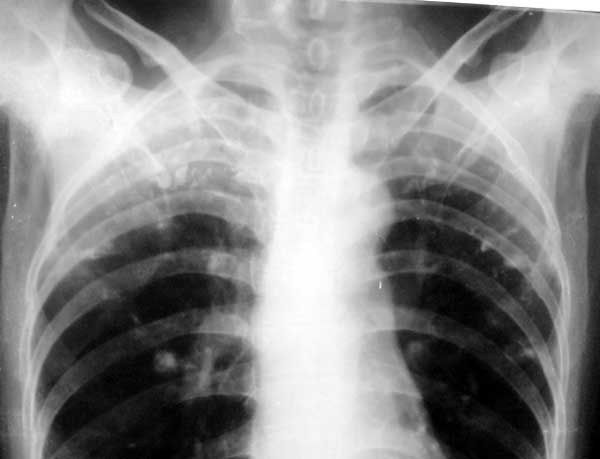

标题: X0226:[原创]两肺结节状高密度

f/63y,胸痛数天,曾患结核性胸膜炎。

2、最后一张胸片,左侧肺门处可以见到云雾状密度增高影,密度均匀,边缘模糊,是什么?

两上肺继发性肺结核;左肺门云雾样高密度影为何物?心后可见结节样高密度影是?请楼主告知详情![emb10]

不好意思,左肺门云雾样高密度影是数码相机摄像的伪影。[emb18]

(第三张片左肺门旁云雾状影楼主已提示为照相时出现的伪影。)

1、双上中继发性肺结核,右侧胸膜粘连;

2、最后一张胸片,左侧肺门处可以见到云雾状密度增高影,密度均匀,边缘模糊,考虑左肺舌段渗出